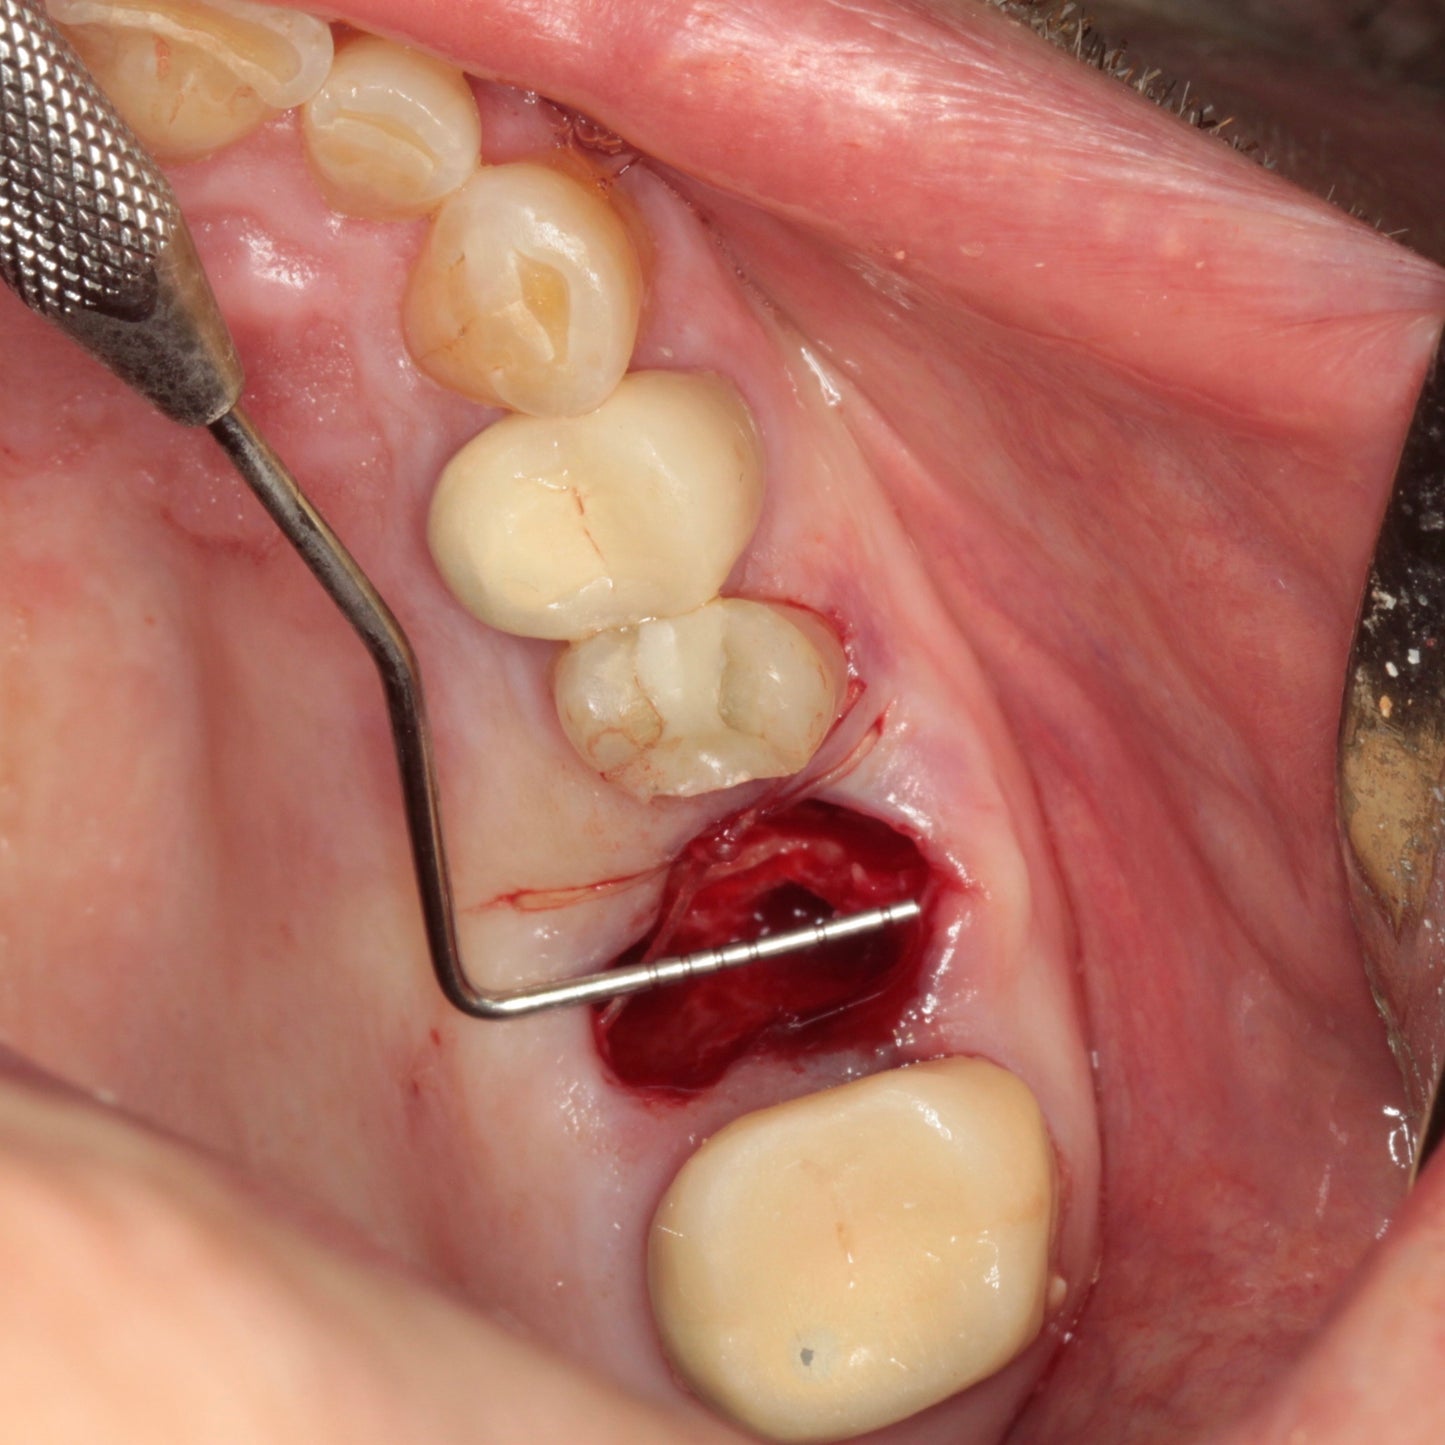

In this course, Dr. Shelemay explains the continuum from extracting a tooth to having a functional and aesthetic implant replacement for the missing tooth. Treatment outcome can greatly improve, and the process simplified by preserving the residual ridge with bone grafting or possibly placing an immediate implant at the time of tooth removal. A systematic approach to classifying extraction sockets helps in determining possible treatment options.Mentors